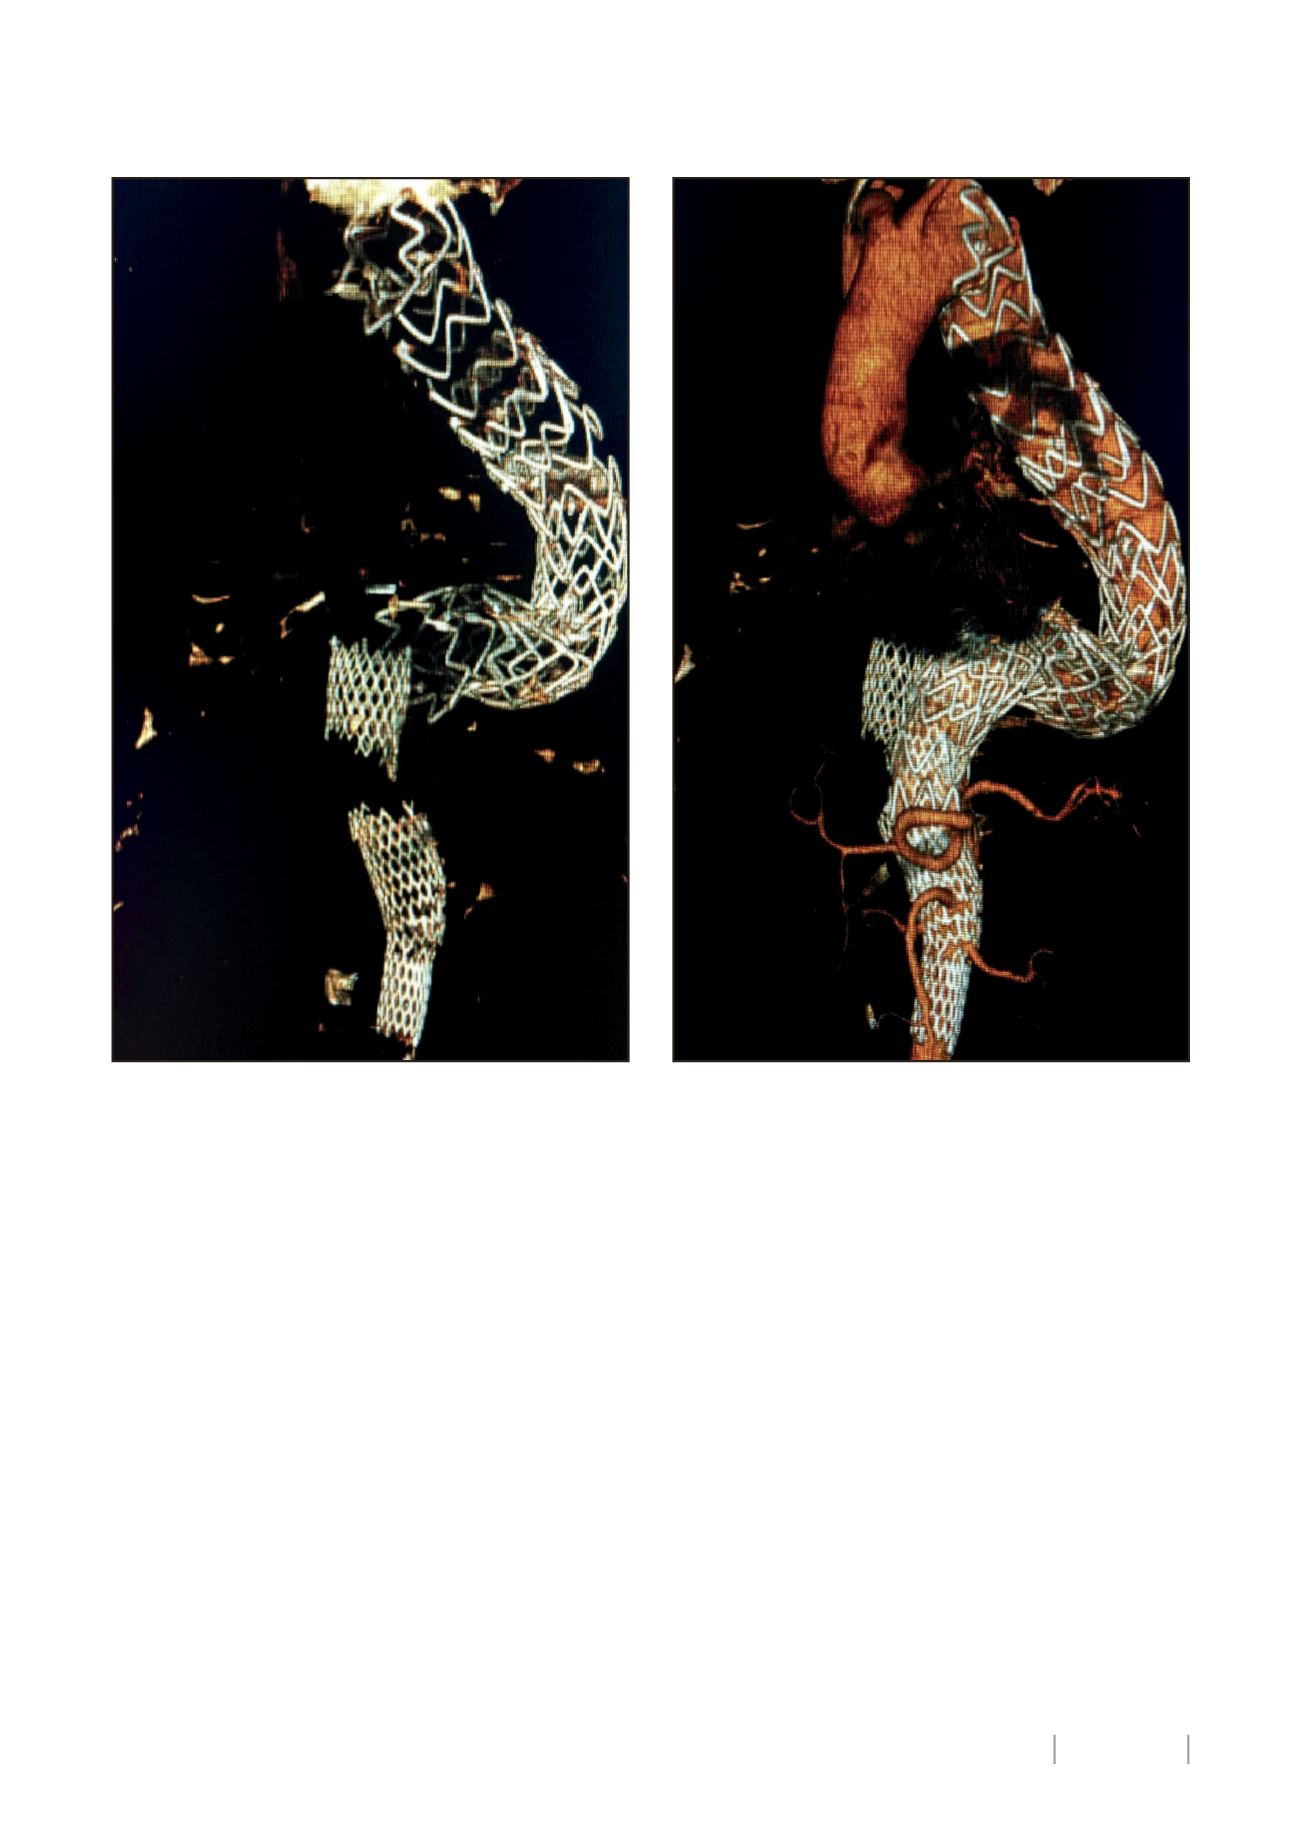

Figura 1. Rotura del stent aórtico con migración craneal de las

endoprótesis, que conlleva repermeabilización del saco aneurismático

por endofuga tipo Ib

Figura 2. Tratamiento endovascular realizado mediante el implante de nue-

va endoprótesis torácica, excluyendo el segmento proximal del stent aórtico

roto, junto con nuevo stent aórtico más embolización del saco aneurismático